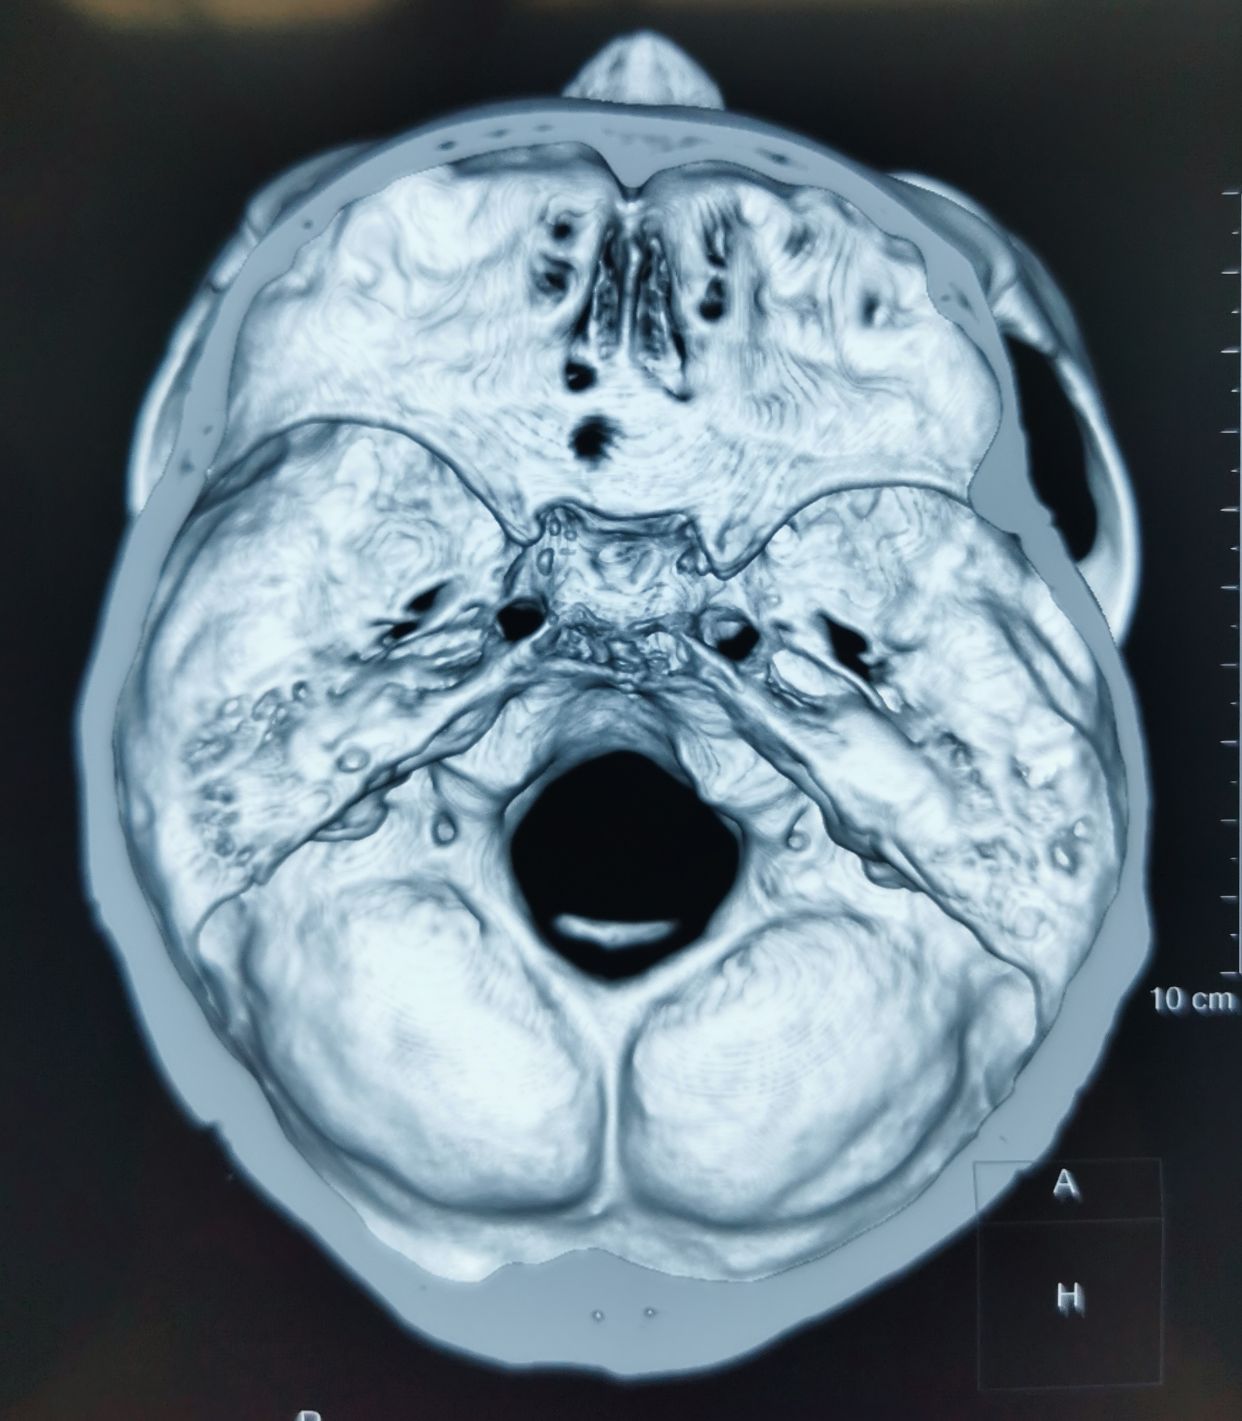

女性,66岁,左侧三叉神经痛

基础疾病多,无法MVD手术,选择PBC

左侧卵圆孔内侧狭小